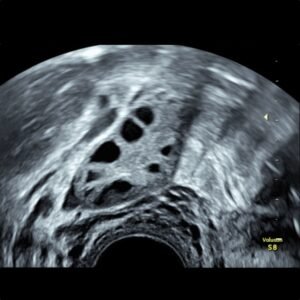

2D ultrazvukom dobivamo dvodimenzionalnu sliku veličine, položaja i morfologije maternice, jajnika i jajovoda te dijagnosticiramo ciste, tumore, upalne procese, unutarmaterničnu i izvanmaterničnu trudnoću itd.

2D ULTRAZVUK